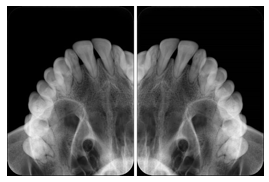

3. A dental provider wishes to capture a series of DICOM IO images for the patient’s dentition. The tooth morphology, teeth are divided into molars, premolars, canines and incisors, and a number of images for each jaw. The anatomic information was captured utilizing the triplet of schema. This standard code sequence is based on ISO 3950-2010, Dentistry - Designation system for teeth and areas of the oral cavity.

Every IO image should have anatomic information either through the primary or modifier sequence.

In most standard cases, images are oriented in structured layouts. These structured displays are useful to be shared between providers for reference purposes.

Table OO.1.1-1 shows structured display standard templates, where Viewset ID is based on the Japanese Society for Oral and Maxillofacial Radiology (JSOMR) classification provided by JIRA (Japan Medical Imaging and Radiological Systems Industries Association, www.jira-net.or.jp). Expected or typical teeth to be imaged location, region and designation codes are based on ISO 3950-2010, Dentistry - Designation system for teeth and areas of the oral cavity. For all the hanging protocols listed in OO.1.1-1, the value to use for Hanging Protocol Creator (0072,0008) is "JSOMR" and the value to use for Hanging Protocol Name (0072,0002) does not include "JSOMR" (e.g., "DL-S001A", not "JSOMR DL-S001A").